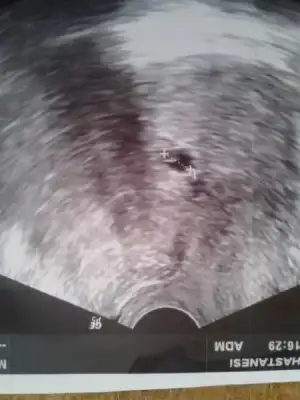

Nolur dikkatli bakın Dr. Embriyo gördü saat 9 bucukta

Ilk resimde Dr. Embriyo gördü 5-6 haftalik kalp anısına haftaya bakalım dedi.

2 ayrı özel hastaneye gittim.saat 9 buçukta dr. cihazı direk tuttu keseyi ölçmedi ama bir hafta öncesine göre büyümüş hatta bak çok belli olmasa da embiriyo oluşmaya başlamış 5-6 haftalık görünüyor 1 hafta sonra kalbi duyarız dedi.kan verdim

ilk resimde oluşuyor gibii![]()